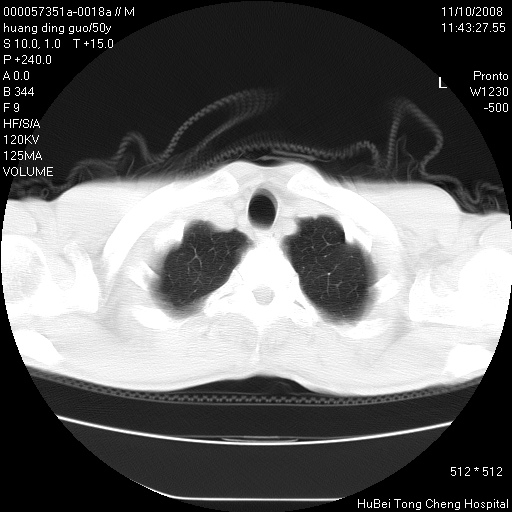

患者 男,50岁。左侧腰背部疼痛3月余,伴消瘦。平素健康,无传染病史。

胸部ct轴位平扫(层厚10mm,螺距1.5,重建间隔10mm),图像如下:

左肺下叶背段有一厚壁空洞,外壁呈锯齿状伴毛刺改变。空洞相邻胸膜有牵拉改变。左肺下叶血管支气管束不规则增粗,小叶间隔增厚。胸椎骨质破坏。考虑左肺下叶周围型肺癌伴左肺下叶癌性淋巴管炎、胸椎转移。

左肺下叶背段有一厚壁空洞,外壁呈锯齿状伴毛刺改变。空洞相邻胸膜有牵拉改变。左肺下叶血管支气管束不规则增粗,小叶间隔增厚。胸椎骨质破坏。考虑左肺下叶周围型肺癌伴阻塞性肺炎、胸椎转移。其他待排

左肺下叶背段有一厚壁空洞,内壁不规则,外壁呈锯齿状伴毛刺改变。空洞相邻胸膜有牵拉改变。周围呈絮状炎性改变,左肺下叶血管支气管束不规则增粗,小叶间隔增厚。胸椎骨质破坏。考虑左肺下叶周围型肺癌伴左肺下叶阻塞性肺炎、胸椎转移。